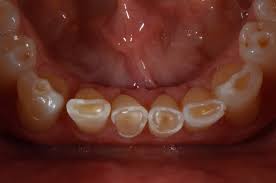

دندان‌ قروچه‌ عبارت‌ است‌ از عادت‌ ساییدن‌ دندانها. دندان‌ قروچه‌ معمولاً در خواب‌ رخ‌ می‌دهد ولی‌ ساییدن‌ یا کوبیدن‌ دندانها در طول‌ روز نیز شایع‌ است‌. دندان‌ قروچه‌ مداوم‌ ممکن‌ است‌ باعث‌ خوردگی‌ لثه‌ها و استخوانهای‌ حمایت‌کننده‌ از آنها در دهان‌ شود. در این بیماری صداهای‌ آزاردهنده‌ دندان‌ قروچه‌ در شب ایجاد می‌شود‌. این‌ صداها ممکن‌ است‌ چنان‌ بلند باشند که‌ دیگران‌ را از خواب‌ بیدار کنند. انقباض‌ فراوان‌ عضلات‌ در یک‌ طرف‌ صورت‌ و در نتیجه خستگی و گاهی درد در عضلات صورت، سایش و آسیب‌ به‌ دندانها، لثه و استخوان‌ حمایت‌کننده‌ آن، لقی دندانها، افزایش درد دندان و حساسیت ،بی خوابی و گاهی سردرد و گوش درد از پیامدهای دندان قروچه می باشند.